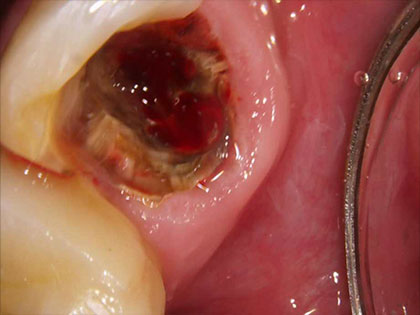

• 治療中の写真がこちら

• インプラント治療中1